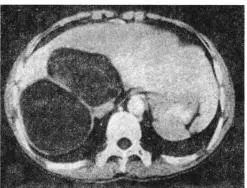

*疆新**医生报道1例,年轻女性,诉咳嗽,咳草绿色痰液,每天约半斤(200~300ml)。入院后发现,每天咳出的液体高达500ml,为胆汁样液体,考虑胆管一支气管瘘。开胸探查术,见膈肌顶部破裂,扩大膈肌破裂口探查肝脏,见肝棘球蚴囊肿。

肝棘球蚴囊肿CT什么样?如下: